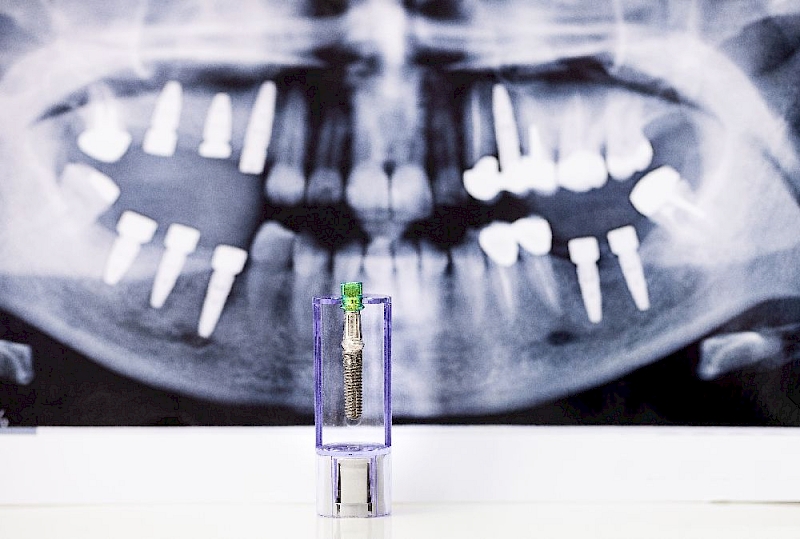

In guided implantology, the 3-dimensional volumetric tomography image and intraoral measurements of the person to be implanted are taken, and the implants are placed in the appropriate bone points according to the guide program.

“It is an implant application that can be placed in the bone as designed on the computer.”

In guided implantology, the 3-dimensional volumetric tomography image and intraoral measurements of the person to be implanted are taken, and the implants are placed in the appropriate bone points according to the guide program. Thus, it is possible to place the implants in the best prosthetic way, shaping their angles and positions with the 3D guide plates prepared before the procedure. Since the end prosthesis is pre-designed on the same planning too, the number of sessions required for the prosthesis after the healing process is minimized without any margin of error.